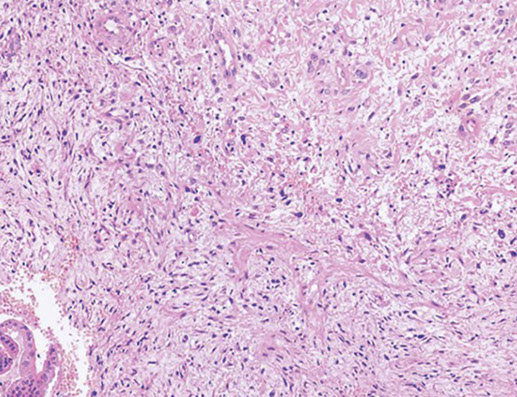

Malignant mixed mullerian tumor (MMMT, carcinosarcoma)

Rare, biphasic high grade tumor with epithelium and stroma which can occur anywhere in female rep tract

- postmenopausal chicks c pelvic pain, ranges from 1-10 cm

- cartilage clinches the dx (? tho may be em ac c focal cartilagenous or osseous metaplasia; differentiate c atypia + mits)

- strong risk factor is pelvic radiation

- several theories exist as to how arises (collision theory, combination theory, composition theory, conversion theory [metaplastic carcinoma c sarcomatous part being made 2/2 inc aggressiveness])

Micro: biphasic, c carcinoma and sarcomatous parts

Epithelial portion can be em, serous, clear cell, undifferentiated, squamous, while stroma can be homologous / heterologous

Homologous: (native to the tumor site) endometrial stromal sarcoma or leiomyosarcoma or undifferentiated sarcoma

Heterologous: (not native to the tumor site) muscle, cartilage, bone, fat

- common to see lymphangio invasion

IHC: (+) keratins (+ in carcinomatous and sarcomatous parts), EMA, p53, vimentin, fibronectin

Tx: TAHBSO if the LNs in pelvis suspicious, rads + chemo, recurrence recur in lungs n abd

Px: 1/3 alive at 5-years

MMMT

Carcinosarcoma